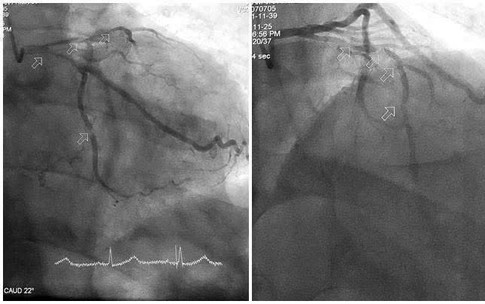

Cứu sống bệnh nhân vỡ động mạch chủ bụng bằng Stent graft

Y tế - 10/10/2025 14:54SKĐS - Vừa qua, các bác sĩ Bệnh viện Hữu Nghị đã cứu sống một bệnh nhân 76 tuổi bị vỡ túi phình kích thước gần 8cm (động mạch chủ) bằng kỹ thuật can thiệp nội mạch hiện đại, đây là một tình trạng cấp cứu y khoa có tỷ lệ tử vong cao.